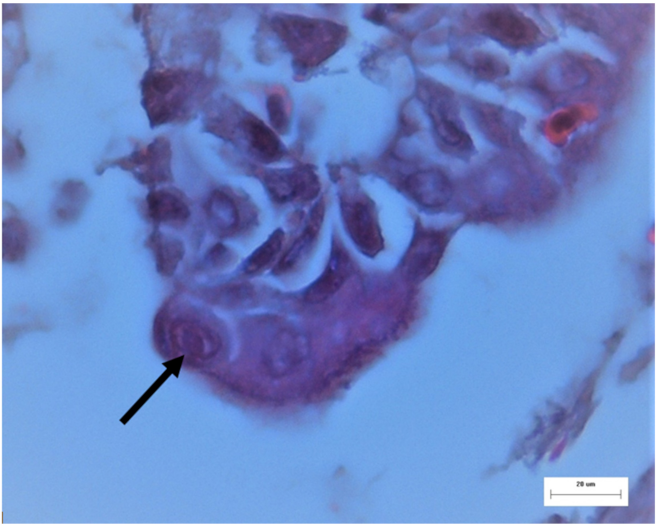

2.4. Histopathological Examination